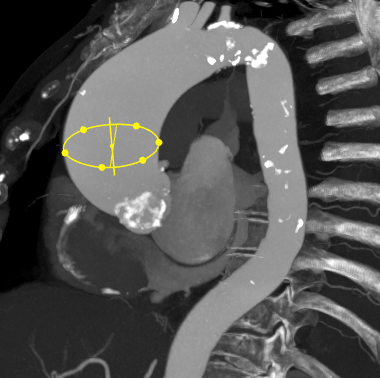

心脏CTA评估显示:Sievers 1型二叶式主动脉瓣,瓣叶明显增厚并重度钙化;瓣环周长82.7mm,瓣环面积534.9mm²;左冠状动脉开口高度12.6mm,右冠状动脉开口高度14.9mm;升主动脉最大直径60mm;横位心,瓣环角度60度。